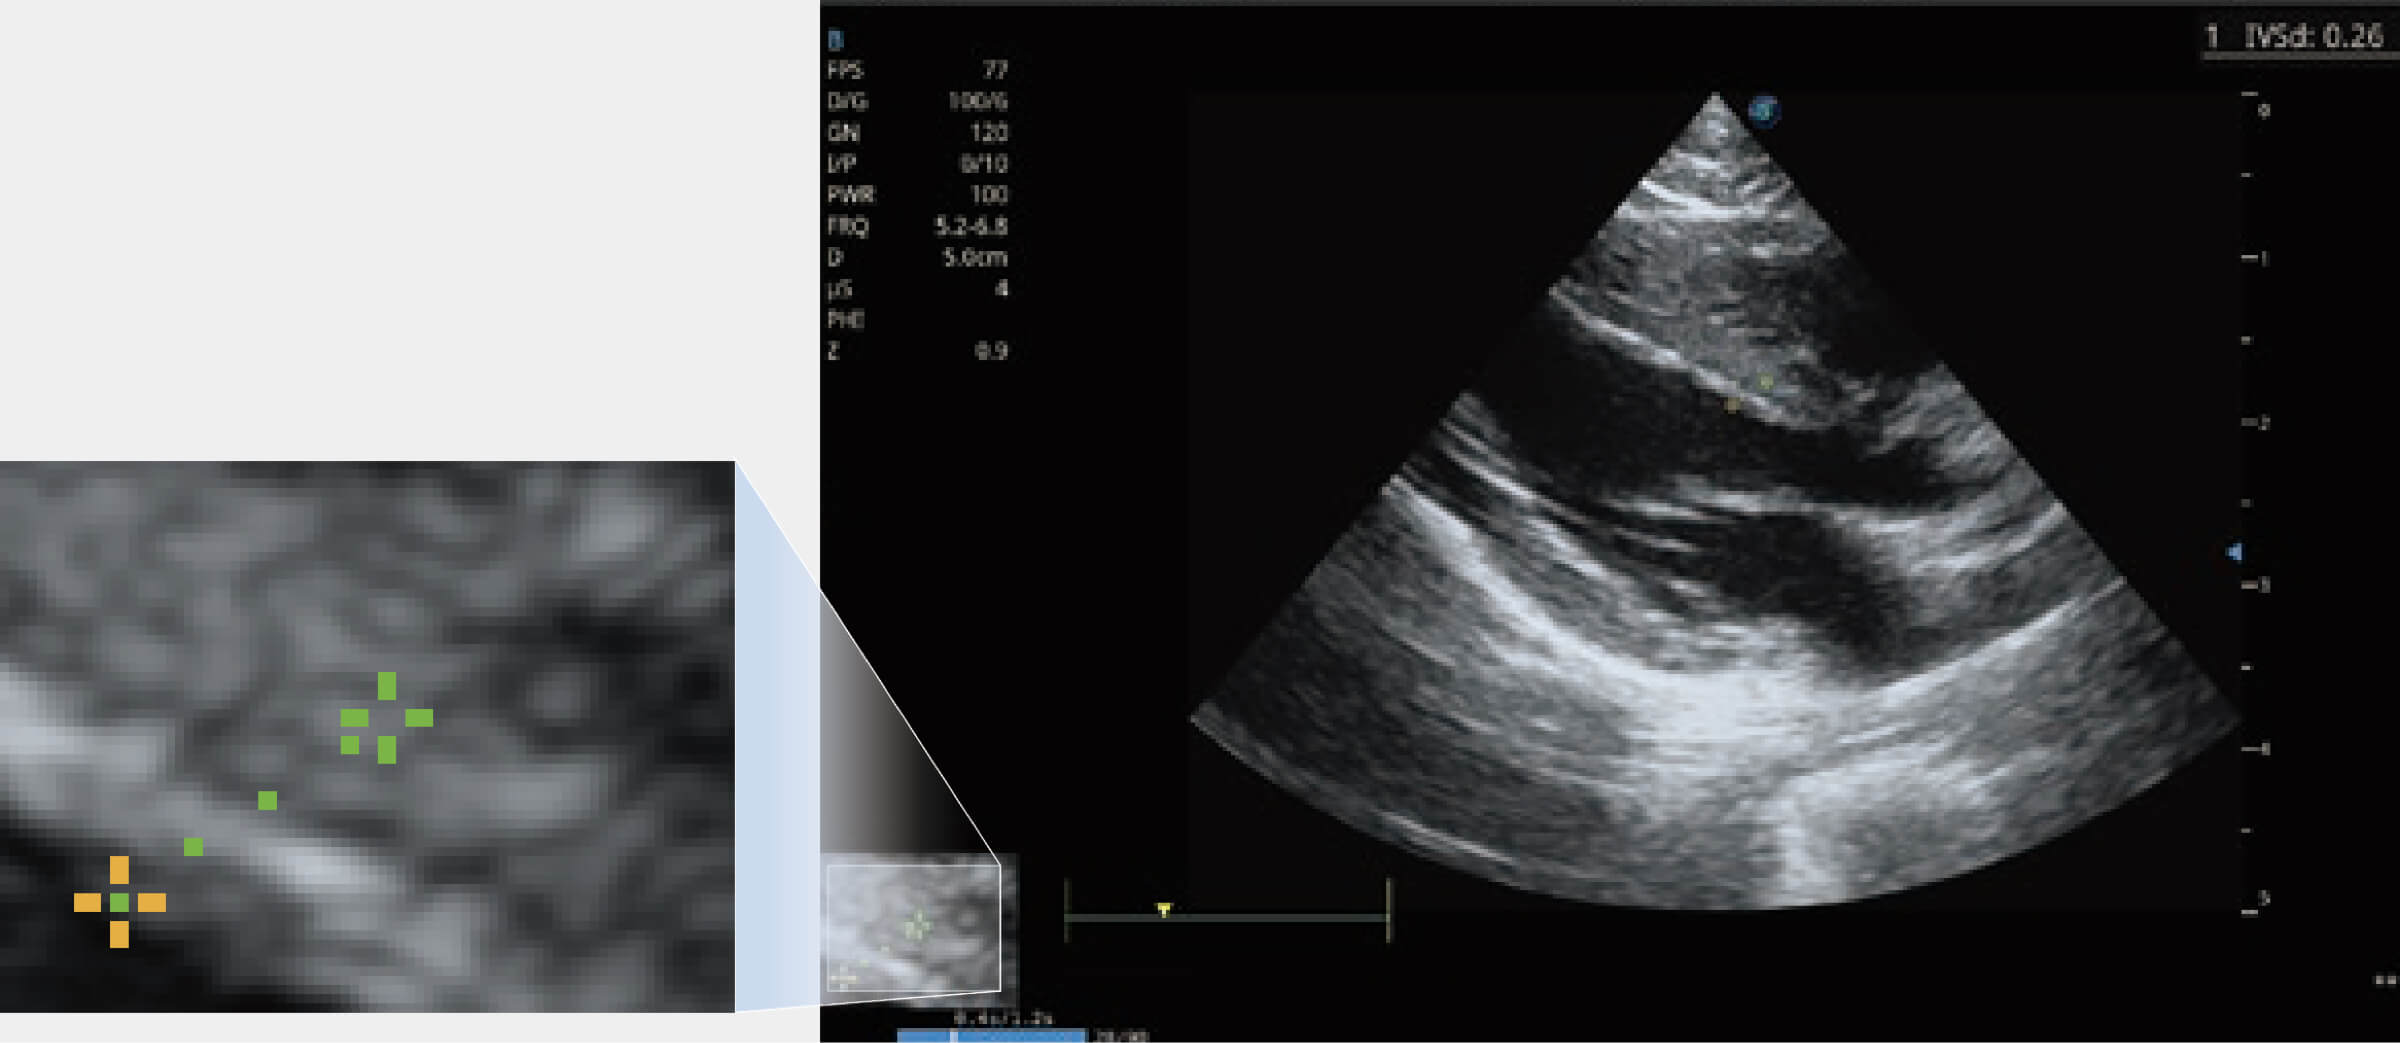

增强穿刺针在动物解剖结构中的位置,提高穿刺介入的安全性和准确性。